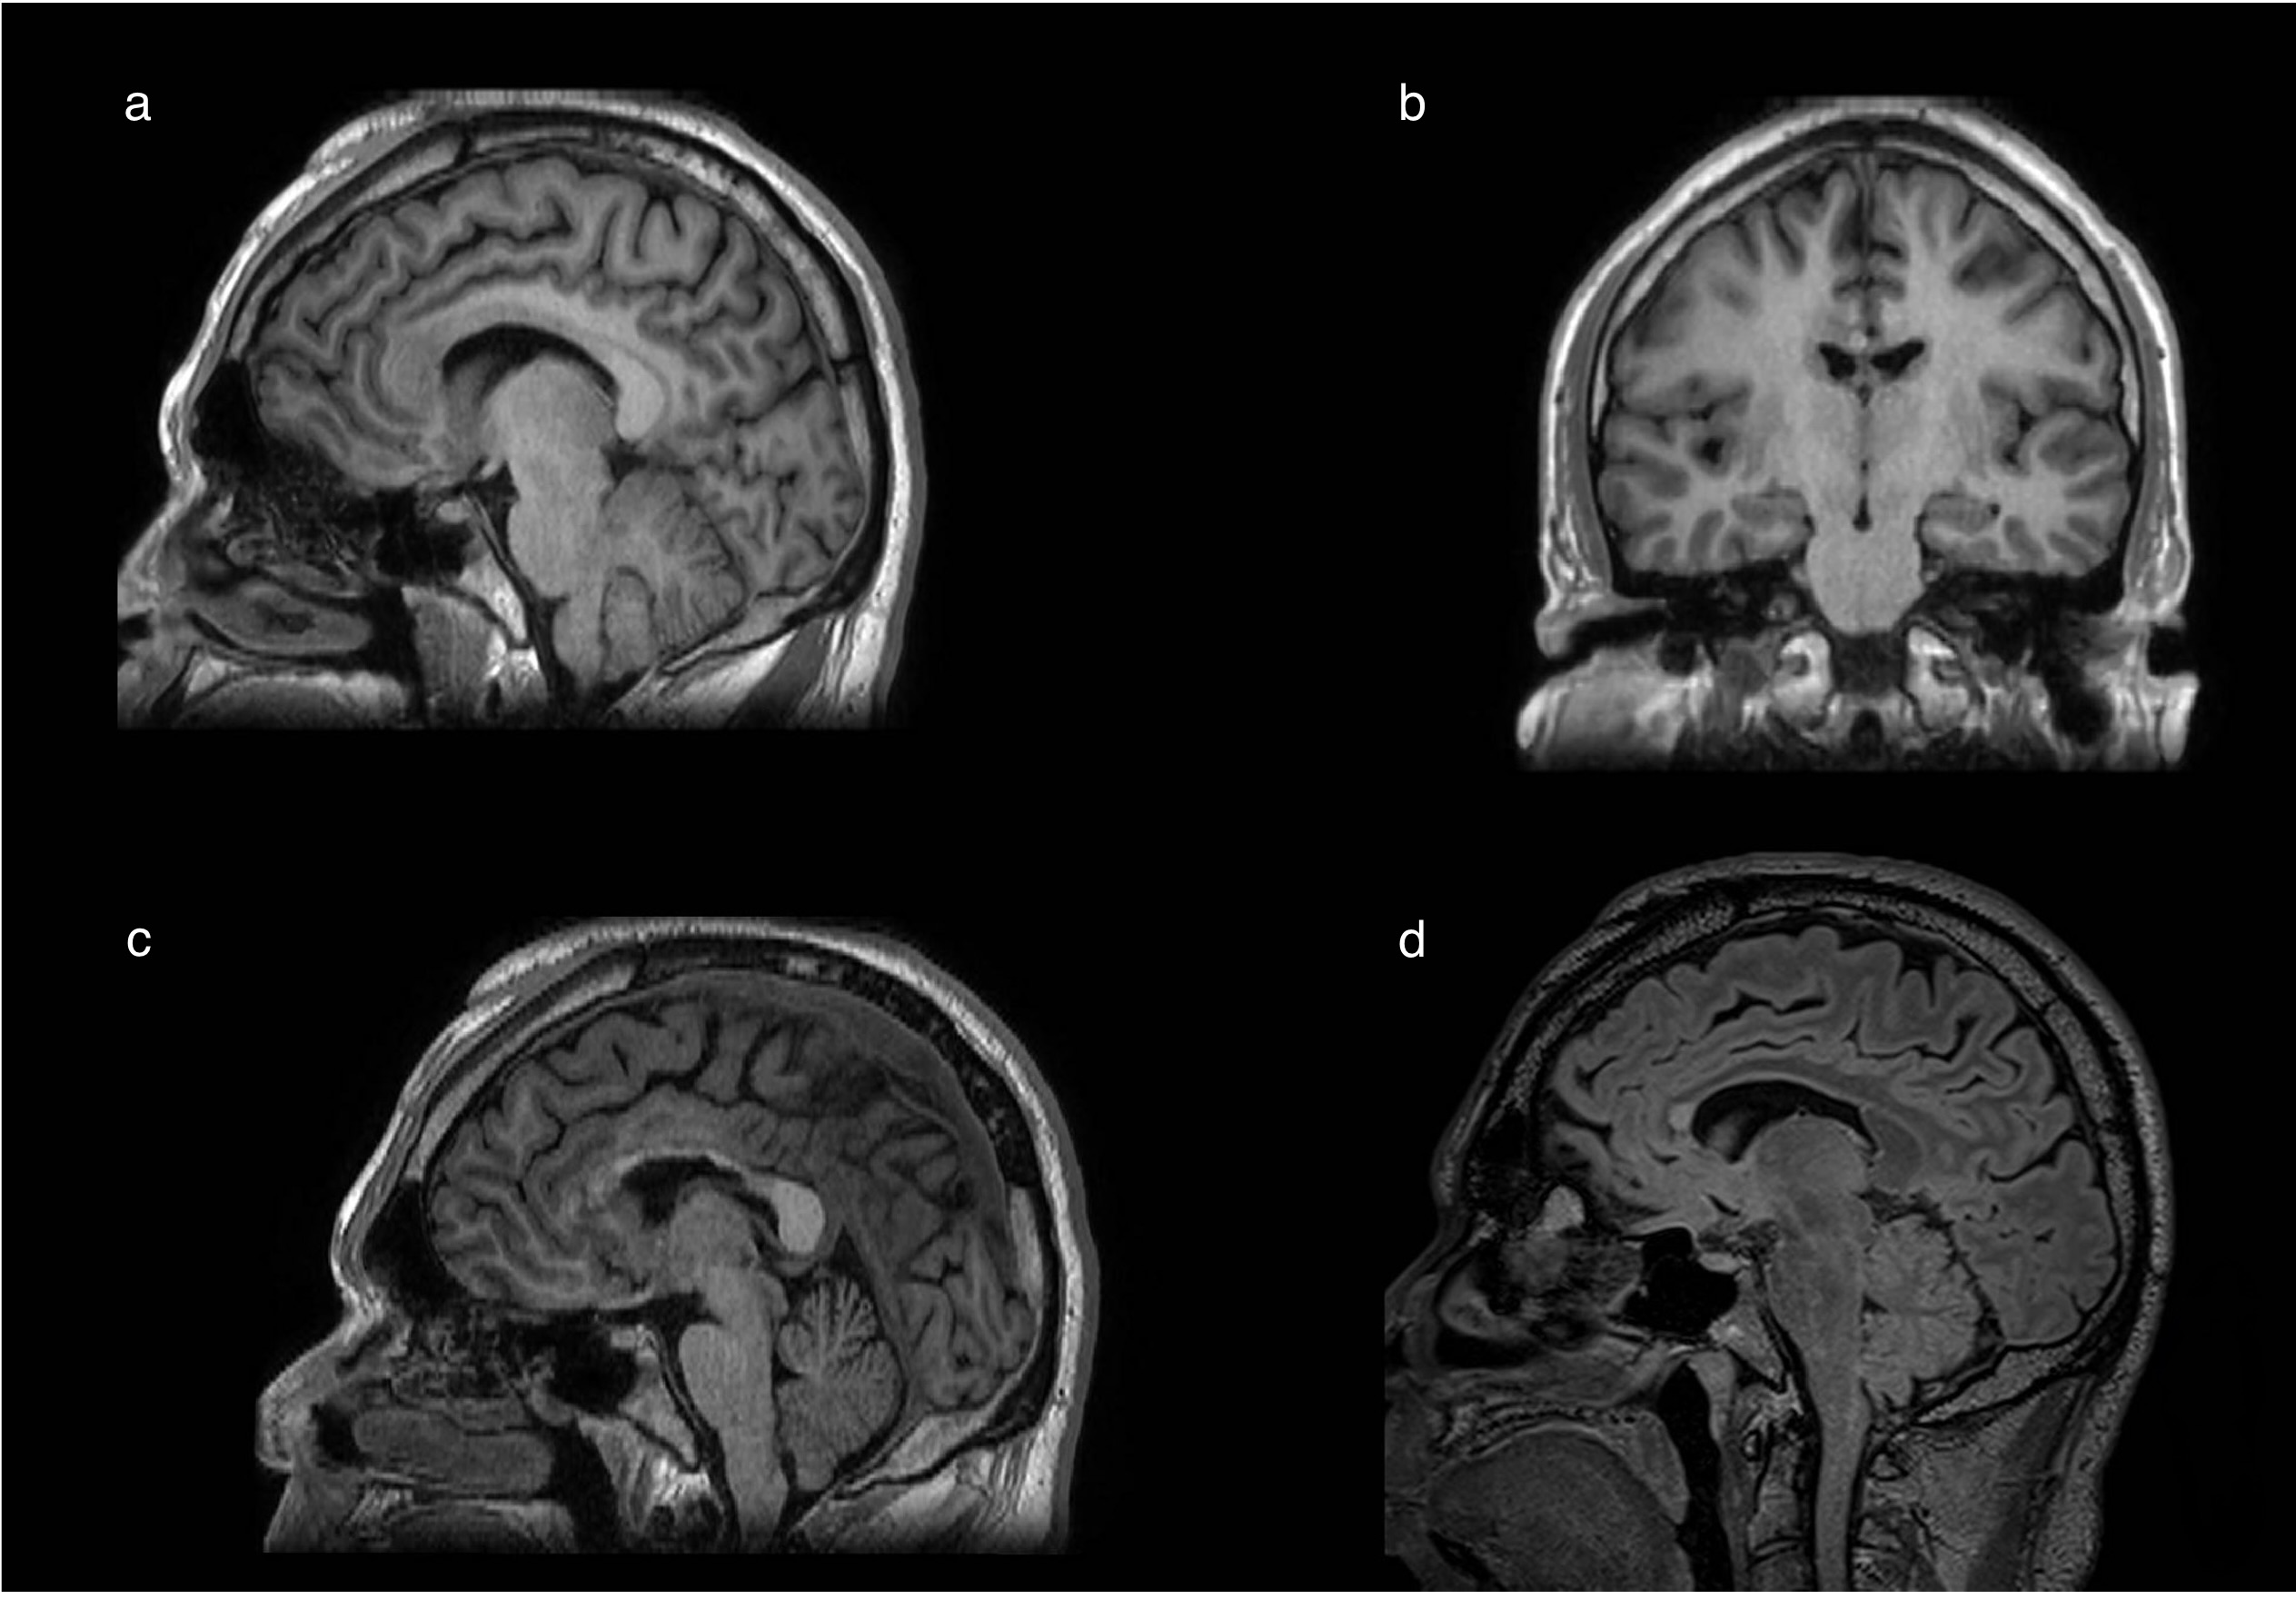

Rationale: Radiosurgical corpus callosotomy (rCC) is a safe and effective palliative procedure for patients with multifocal refractory epilepsy with tonic/atonic and another generalized seizures, however, 10-30% patients fail to this procedure, searching additional inter-hemispheric disconnection strategies including the disconnection of the “massa intermedia” (MI), has not been explored in humans. This study aims to provide initial evidence of the effect of add-on disconnection of the MI in adult candidates for rCC.

Methods: : A cohort study was conducted involving 13 adults diagnosed with drug resistant epilepsy candidates to rCC, categorized into two groups: rCC only (CA group n=10) and rCC with interthalamic adhesion disconnection (AD group, n=3) using linear accelerometers. The outcomes were the post-operative seizure control using the Ougini scale and the rate of adverse events evaluated at least during 1 year of follow-up.